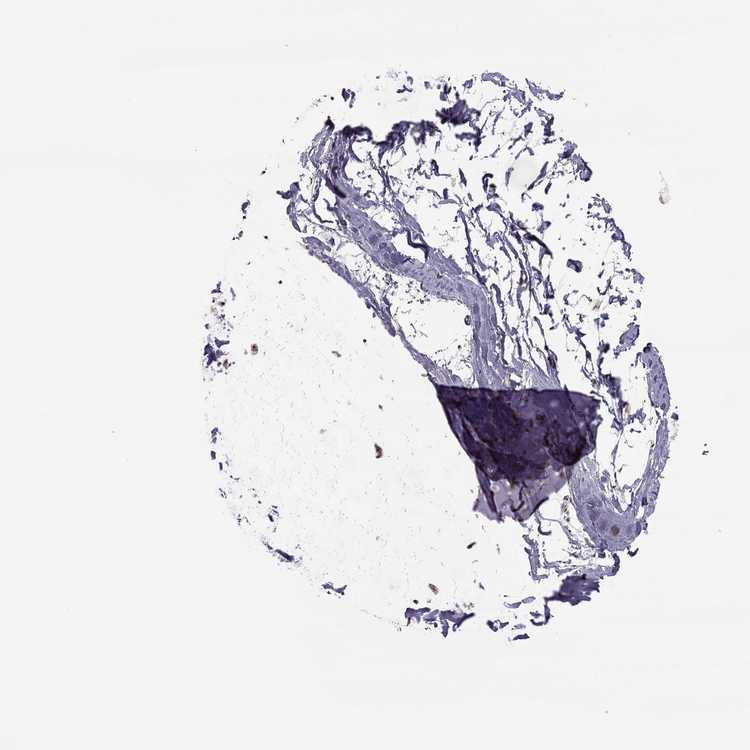

TISSUE PRIMARY DATA SOFT TISSUE Show tissue menu

SOFT TISSUE - Expression summary

SOFT TISSUE 1 - Antibody stainingi

Antibody staining in the annotated cell types in the current human tissue is reported as not detected, low, medium, or high, based on conventional immunohistochemistry profiling in selected tissues. This score is based on the combination of the staining intensity and fraction of stained cells.

Each image is clickable and will lead to virtual microscopy that enables deeper exploration of all samples and also displays staining intensity scores, fraction scores and subcellular localization as well as patient and tissue information for each sample.

Antibody HPA019238Antibody HPA049621

Chondrocytes Low-

Fibroblasts Not detectedMedium

Peripheral nerve Not detected-

SOFT TISSUE 2 - Antibody stainingi

Fibroblasts LowHigh

Peripheral nerve Not detectedMedium